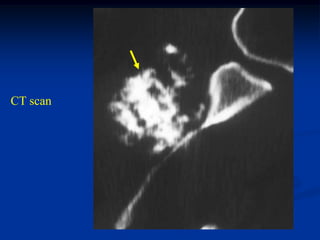

Case #617

26 year male with osteochondroma proximal fibula

Lateral view